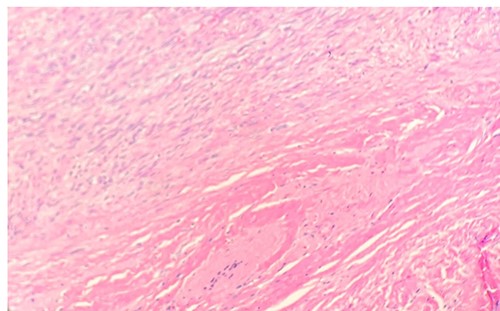

Per gross report, the mass measured 3.5 cm. The mass was biopsied, which showed an infiltrative tumor involving skeletal muscle and composed of large, epithelioid cells with abundant, granular cytoplasm (Fig. 1), indicating the typical features of granular cell tumor. In the central aspect of the mass, a proliferation of monomorphic myofibroblast-like spindle cells in streaming fascicles were found (Fig. 1), also indicating the typical features of desmoid-type fibromatosis. Additionally, the granular cells showed pale basophilic to amphophilic cytoplasm. No pleomorphism was noted. The microscopic examination of the excised mass revealed various morphological tumor cells. Immunohistochemical stains showed that the epithelioid cells are positive for S100 (Fig. 2) and CD68 and negative for pan-cytokeratin. The spindle cells are focally positive for SMA in a myofibroblastic pattern.

Microscopic examination reveals long sweeping fascicles with uniform elongated, slender, spindled cells with pale cytoplasm in a collagenous stroma (left upper- desmoid-type fibromatosis). Sheets of uniform epithelioid cells with abundant eosinophilic granular cytoplasm and small nuclei (right lower-granular cell tumor) (H&E 10x).